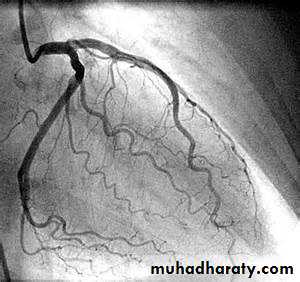

Cardiac catheterisation

This involves passage of a preshaped catheter via a vein or artery into the heart under X-ray guidance, which allows the measurement of pressure and oxygen saturation in the cardiac chambers and great vessels, and the performance of angiograms by injecting contrast media into a chamber or blood vessel

Coronary Angiography